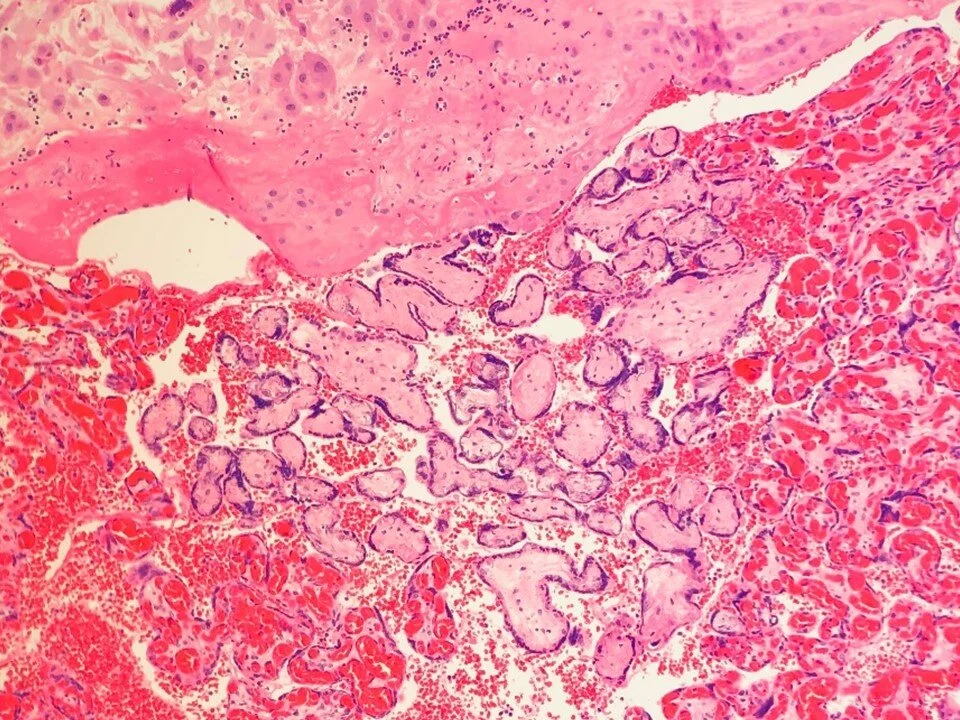

Acute chorioamnionitis: neutrophils extend into fibrous chorion

Chorionic vasculitis - inflammation involves chorionic plate vessels

Can be associated with placental abruption, umbilical cord occlusion, or difficult manual extraction